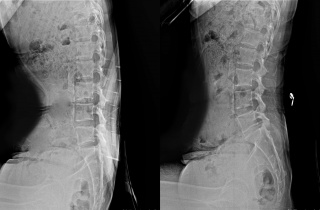

Ãß³ª¿ä¹ý ¿ø¸® Âø¾È 'Ç㸮º¸È£Äí¼Ç' Ãâ½Ã

[µ¥Àϸ®¸Þµð ¹ÚÁ¤¿¬ ±âÀÚ] ÀÚ»ýÇѹ溴¿ø °ü°è»ç ÀÚ»ý¹ÙÀÌ¿À´Â ÀÏ»ó»ýȰ ¼Ó ôÃßÀÇ ¿Ã¹Ù¸¥ ÀÚ¼¼ À¯ÁöÀ» µ½´Â Ç㸮Äí¼Ç ‘ÀÚ2019-09-02 11:45:00